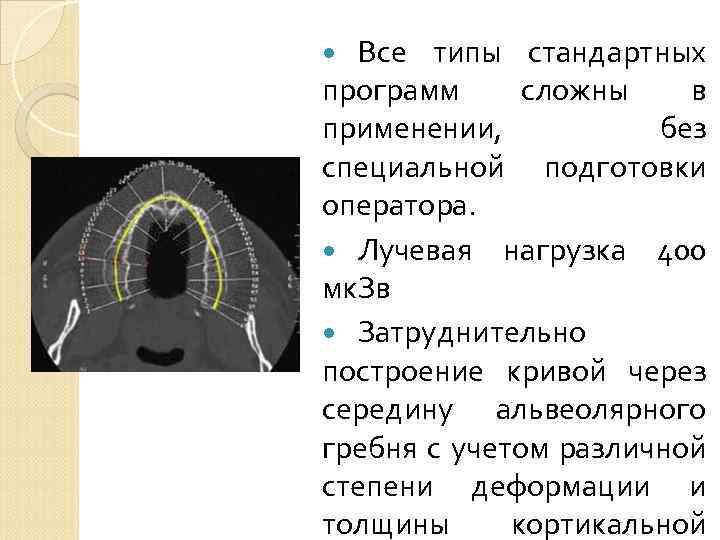

Все типы стандартных программ сложны в применении, без специальной подготовки оператора. Лучевая нагрузка 400 мк. Зв Затруднительно построение кривой через середину альвеолярного гребня с учетом различной степени деформации и толщины кортикальной

Все типы стандартных программ сложны в применении, без специальной подготовки оператора. Лучевая нагрузка 400 мк. Зв Затруднительно построение кривой через середину альвеолярного гребня с учетом различной степени деформации и толщины кортикальной